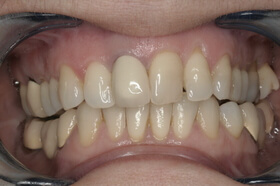

Agresszív fogágybetegség miatt kialakult frontfog elmozdulás – elülső nézet

Agresszív fogágybetegség miatt kialakult frontfog elmozdulás – oldalnézet